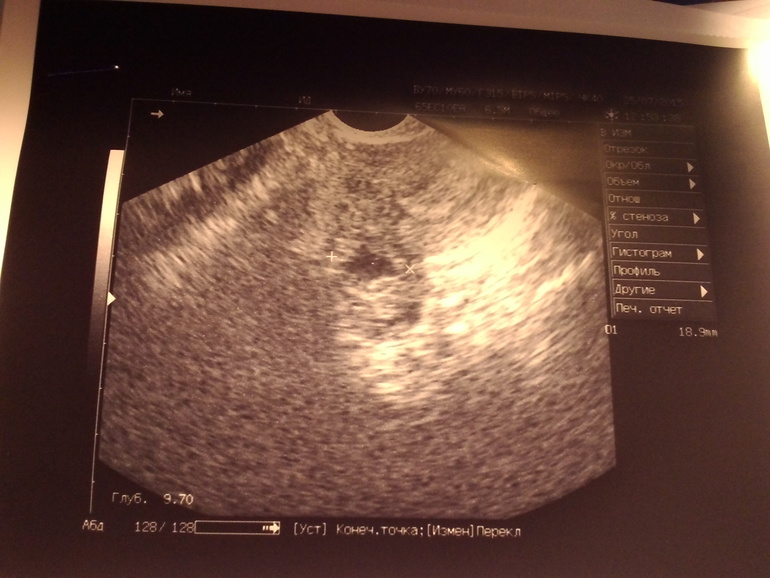

Узи Желтое тело или эндометриоидная киста?

18дц, решила сходить на узи по приезду с юга.2 месяца назад другой узист заподозрила у меня эндометриоидную кисту(год назад такую удаляла).А вот сегодня пошла к своей узистке и она говорит, что похоже на желтое тело и всвязи с 18дц сказать сложно.Сказала приходить на 5 дц, если месячные придут.Мне кажется 18мм мало для желтого тела(( Есть тут те, кто разбирается?

Да нет, действительно похоже на желтое тело, ведь эндометриоидные кисты немного иначе выглядят на УЗИ, они имеют плотную капсулу, более напряженные, нежели данное образование. но контроль, конечно, необходим

ЖТ может быть и 13ммпросто со временем оно начинает цвести и увеличивается в размерах18мм вполне нормальных размеров ЖТ

Мне кажется тоже что за ЖТ вполне сойдет 18 мм